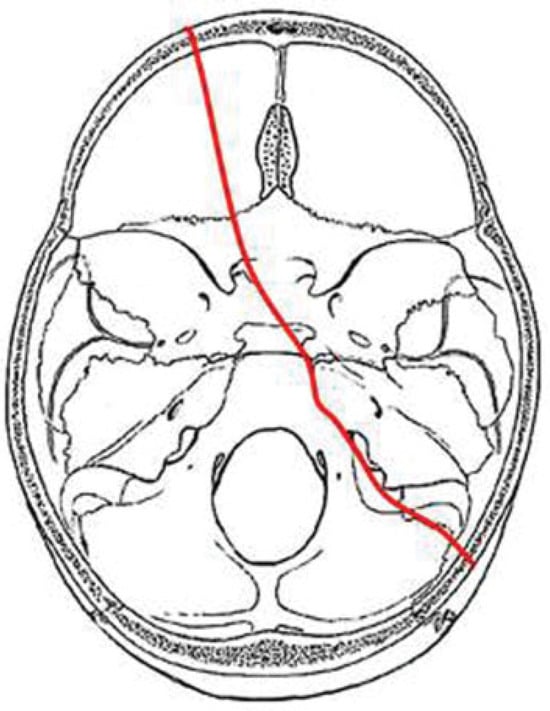

In our study we identified four major fracture patterns of transsphenoidal basilar skull fractures, which were: anterior transverse (AT), lateral frontal diagonal (LFD), posterior trans-verse (PT), and mastoid diagonal (MD), which matches Clark’s descriptions of the transsphenoidal basilar skull fractures.17

AT Pattern

The key to the identification of the AT pattern is the demon-stration of a coronal fracture through the sphenoidal plane at the base of the anterior clinoid processes. The exact position across the anterior sphenoid body varies slightly from the sphenoidal limbus to the roof of the extreme posterior ethmoid air cells. Most fractures pass through the roof of the sphenoid sinus anteriorly. The fracture typically begins in the squamous portion of the temporal bone, courses anteriorly to the sphenotemporal buttress, and then proceeds medially along the orbital surface (vertical plate) or the anterior cerebral surface (horizontal plate) of the sphenoid bone. The fracture intersects the sphenoid body at or slightly posterior to the junction, with the ethmoid bone producing the characteristic transverse fracture across the posterior aspect of the floor of the anterior cranial fossa. The fracture exits the sphenoid body through a similar pathway involving the contralateral greater wing along the orbital surface (horizontal plate) or the anterior cerebral surface (vertical plate). In severe fractures, the fracture will continue to propagate into the contralateral squamous portion of the temporal bone (Figure 5).

Figure 5. Composite drawing of the anterior transverse fracture pattern (left impact).